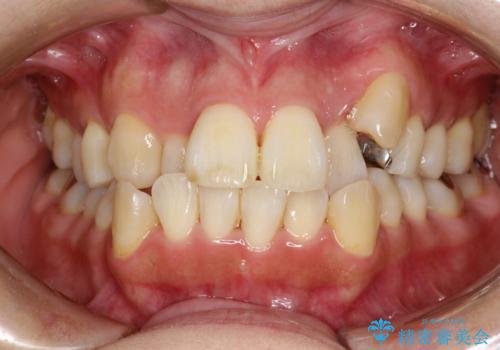

- これから矯正治療を始めるため、今の状態でも歯をきれいにしておきたいとのことでした。PMTC60分コースを行いました。

プラーク(細菌の塊)や歯石がたまると歯の表面はザラつきいてきます。そのザラつきは歯周病や虫歯菌の棲家となります。そのまま放置すると、歯肉が腫れてきたり、歯肉から出血したり、口臭が強くでたりします。とくに歯肉の境目は、歯磨きで汚れを除去することが難しく、プラーク(細菌の塊)や歯石が溜まりやすい場所です。

歯並が、がたついている場合はなおさら汚れが溜まりやすいです。矯正治療前や矯正中、定期的にPMTCをすることで、矯正治療中の歯肉トラブルを防ぐことにつながります。